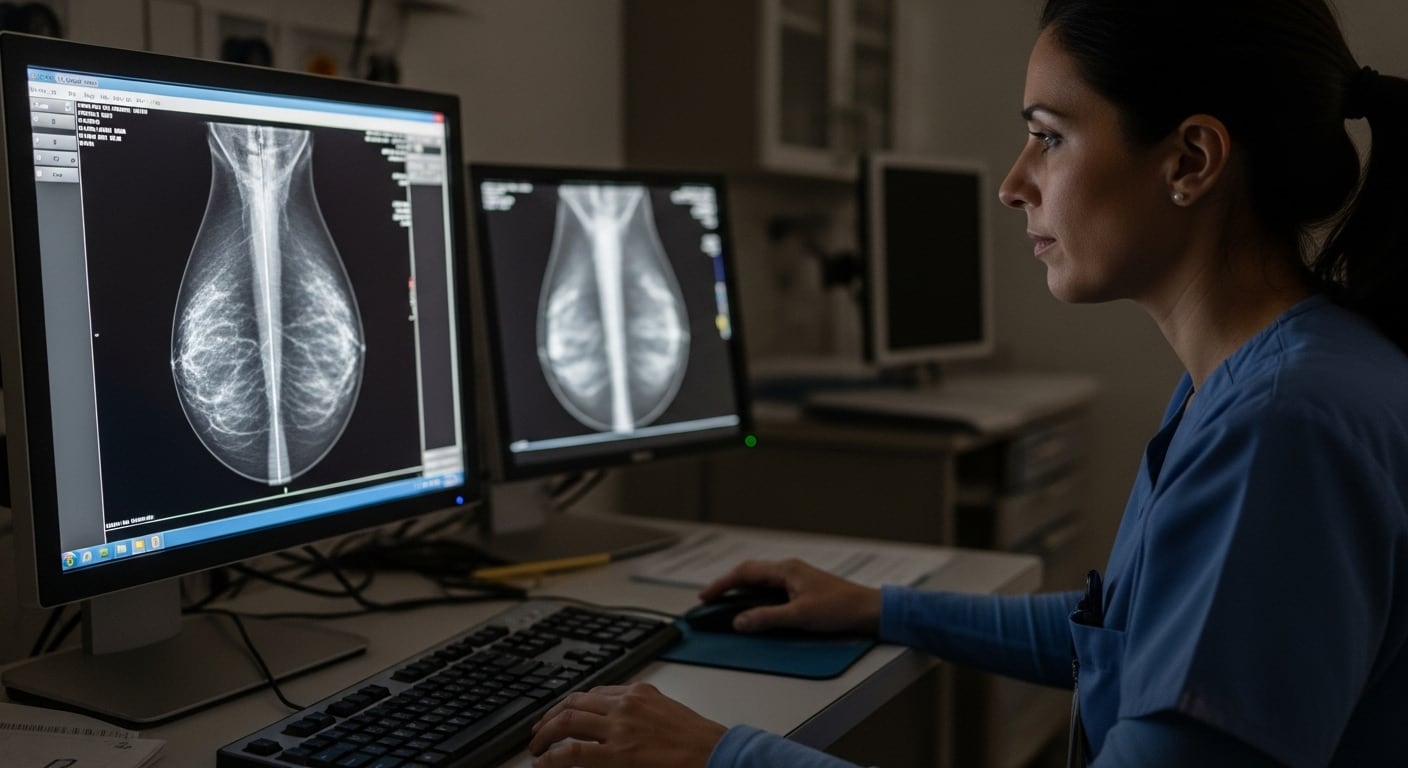

La mayoría de las mujeres continúa identificando el cáncer de mama como su principal amenaza para la salud, aunque la evidencia epidemiológica señala que las enfermedades cardiovasculares son la primera causa de muerte femenina.

Frente a este desajuste en la percepción de riesgo, la incorporación de inteligencia artificial (IA) en las mamografías abre una vía innovadora para anticipar y reducir tanto el riesgo de cáncer como el de patologías cardíacas.

Según recientes investigaciones publicadas en el European Heart Journal, la mamografía asistida por IA permite una prevención dual y oportuna de las principales amenazas para la salud de la mujer.

La aplicación de IA en el análisis de mamografías facilita la identificación automática de la calcificación arterial mamaria (CAS), un marcador que se consolidó como predictor independiente de eventos cardiovasculares adversos. Esta tecnología permite que, durante la rutina de cribado mamográfico, se evalúe simultáneamente el riesgo de enfermedad cardíaca, sin necesidad de estudios adicionales ni exposición extra a radiación.

La mamografía es una de las pruebas de cribado más aceptadas entre mujeres de 40 a 70 años: más del 65% de esta población en Europa y Estados Unidos la realiza según las últimas estadísticas. Este alto grado de adherencia representa una oportunidad única para identificar simultáneamente el riesgo de cáncer de mama y de enfermedad cardiovascular en la misma exploración.

En los últimos años, herramientas y algoritmos de IA como Transpara, DeepHealth, CLARITY Breast y CureMetrix han sido validados y autorizados por la Administración de Alimentos y Medicamentos de Estados Unidos (FDA) para el análisis integral de mamografías. Estos sistemas permiten detectar lesiones sospechosas y, al mismo tiempo, cuantificar la calcificación arterial, generando alertas para la intervención preventiva temprana.